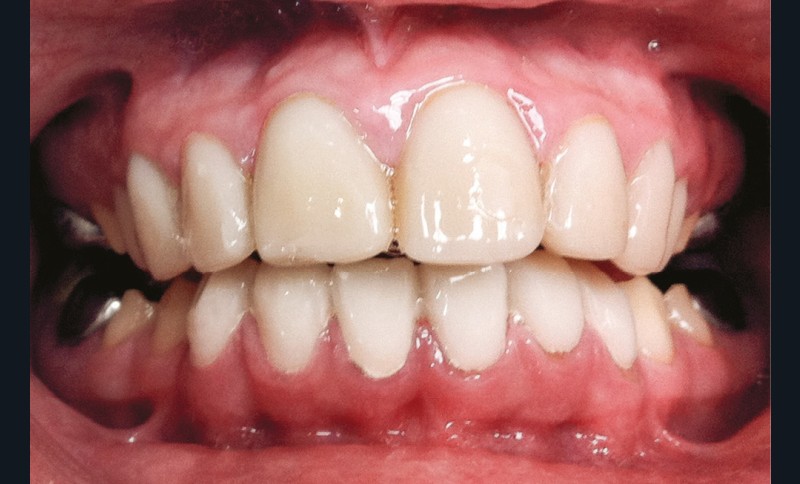

Une patiente âgée de 12 ans a été adressée au cabinet pour « une prise en charge complète sur le long terme » par son praticien traitant. Elle était accompagnée par sa mère. Elle présentait des couronnes transitoires en résine sur le secteur incisivo-canin au maxillaire ainsi que les premières prémolaires, des coiffes pédodontiques métalliques sur les premières molaires, une absence totale d’émail sur l’ensemble de la denture, à l’exclusion des bords libres des incisives mandibulaires (fig. 1 à 3). Le bloc incisivo-canin mandibulaire avait bénéficié de traitements radiculaires (fig. 4). Les incisives maxillaires présentaient des rhizalyses d’une importance significative (fig. 5 et 6). La patiente se plaignait d’hypersensibilités à la mastication et au brossage, la demande esthétique était forte.